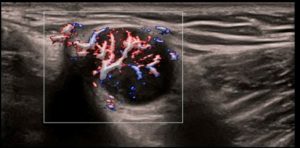

CEUS prostaty

Vyhodnotenie perfúzie mikrocirkulácie na diagnostiku rakoviny prostaty. Technológia UWN+, vysoká citlivosť, dlhá doby perfúzie.